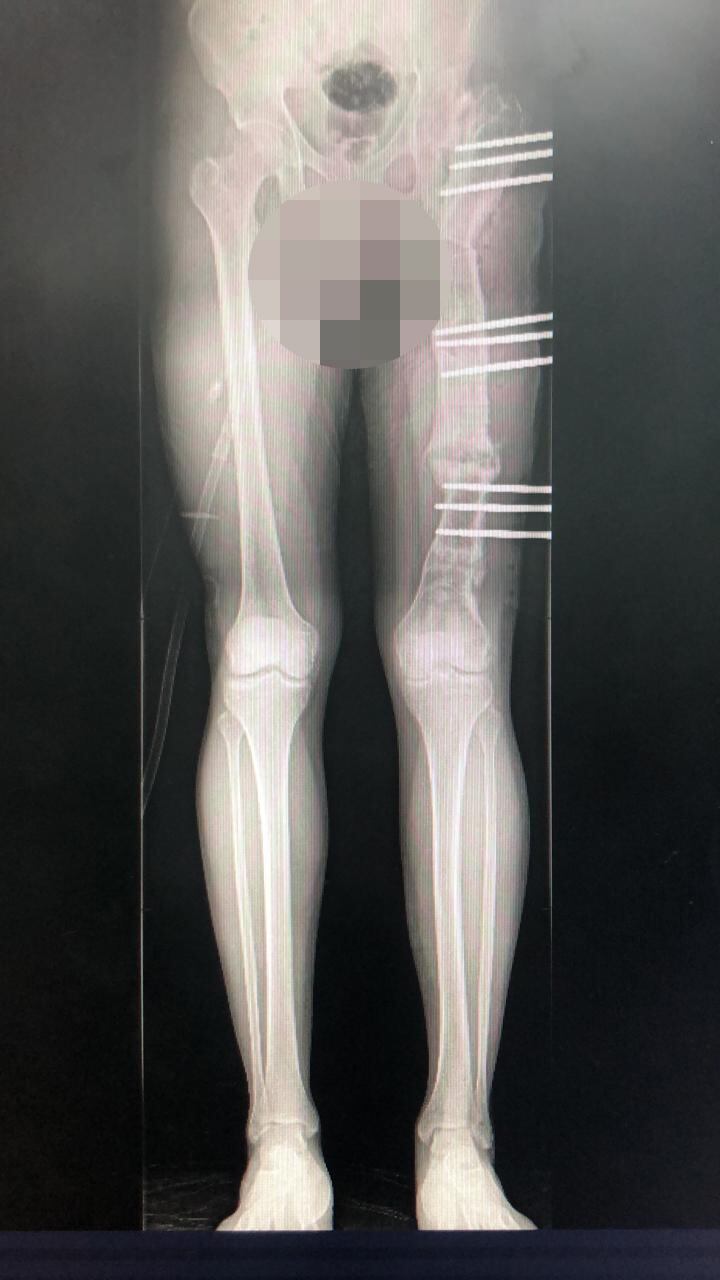

El paciente dice que debido al suceso su tibia quedó más corta y en la operación de esta semana le volvieron a quebrar el hueso y le pusieron unos fijadores externos para guiar la tibia mientras se regenera.

“El tutor (aparato ortopédico externo con pines) que me pusieron es ajustable y la idea es ir adaptándolo cada cierto tiempo para corregir un desvío que tiene la tibia, ya que además de más corta, está hacia adentro.